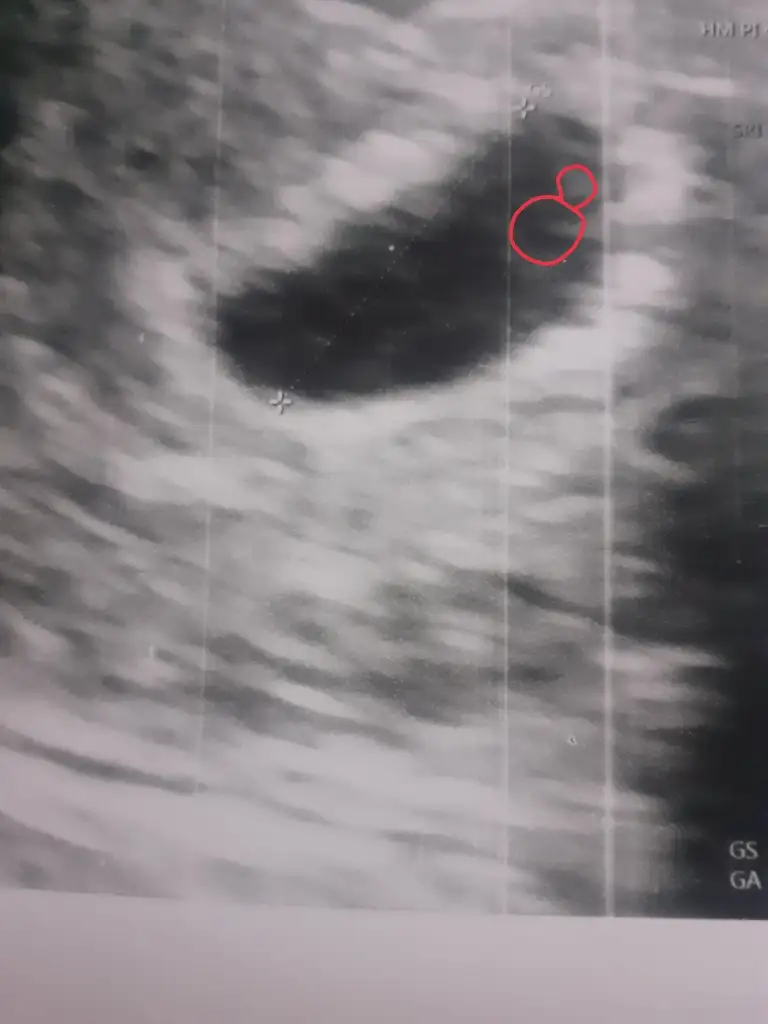

Kızlar benim kesenin içinde birsey görüyor musunuz peki 🥹🧡

Bende o yüzük gibi şeyden yok o ne demek onu da bilmiyorum kızlar biri bakabilir mi😄